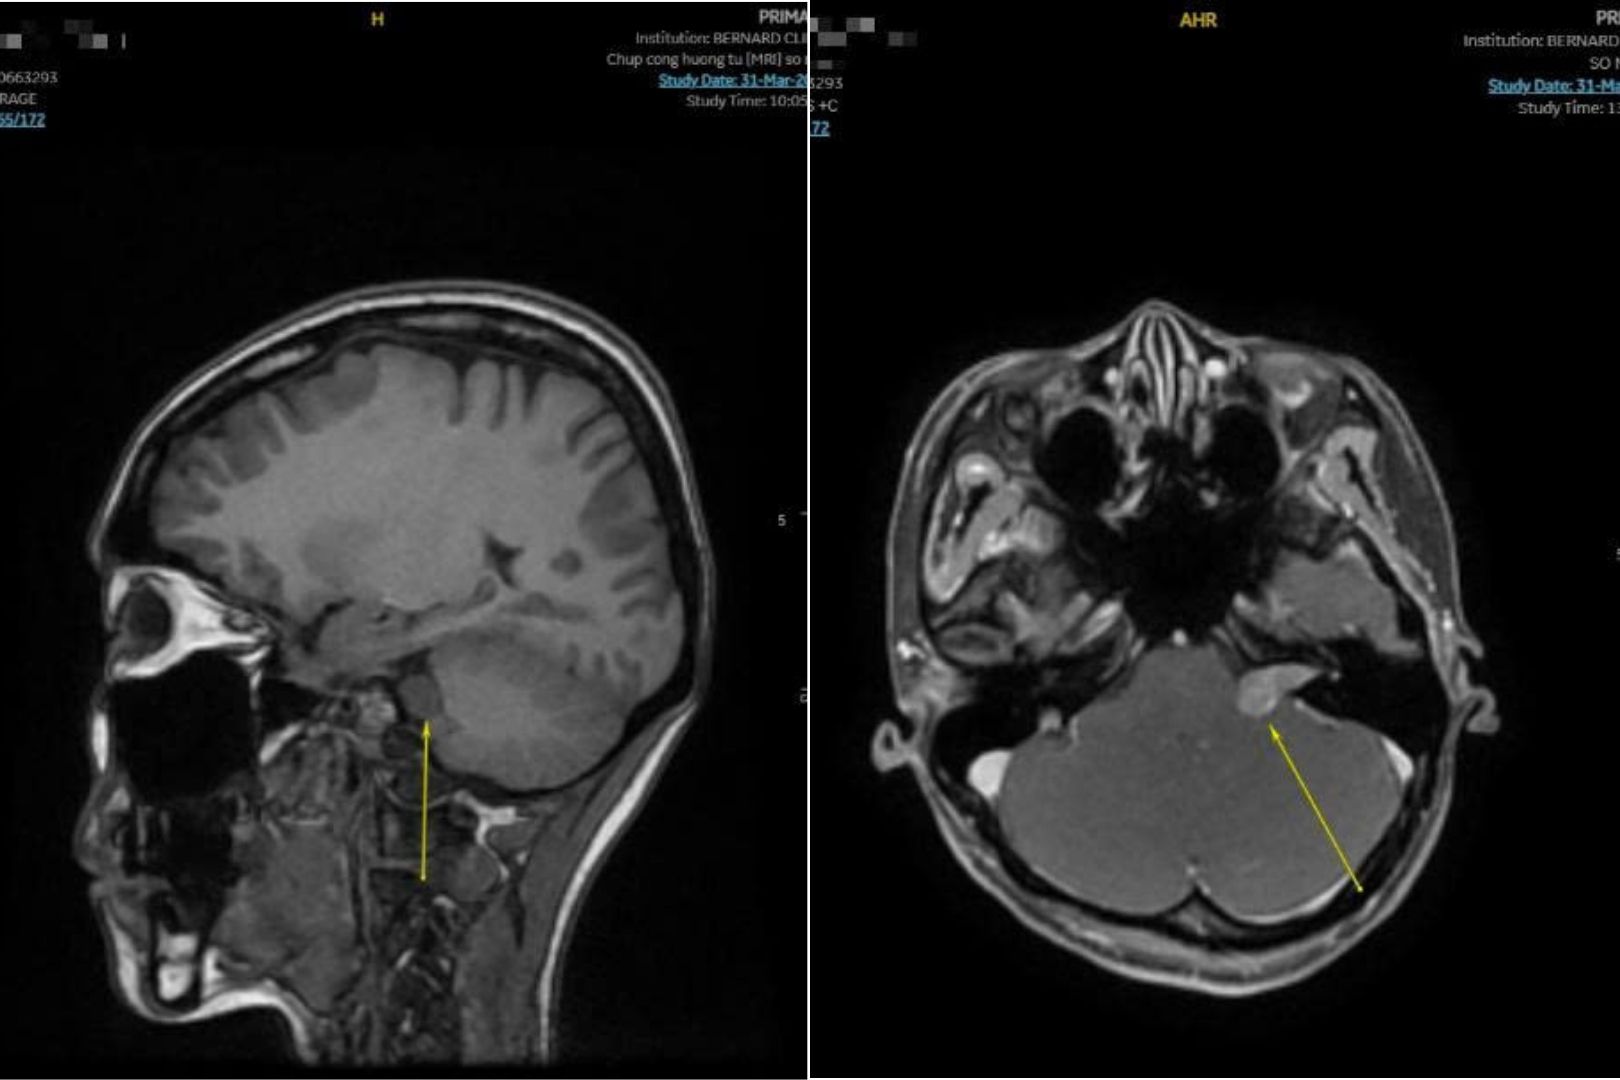

Kết quả MRI cho thấy khối choán chỗ vùng góc cầu - tiểu não trái, lan vào ống tai trong, kích thước khoảng 10x12x20 mm. Các cấu trúc não, đường giữa và não thất vẫn trong giới hạn bình thường.

Bác sĩ kết luận bệnh nhân có u bao dây thần kinh (Schwannoma). Đây thường là u lành tính nhưng dễ gây mất thính lực, rối loạn thăng bằng và biến chứng thần kinh nếu phát hiện muộn.